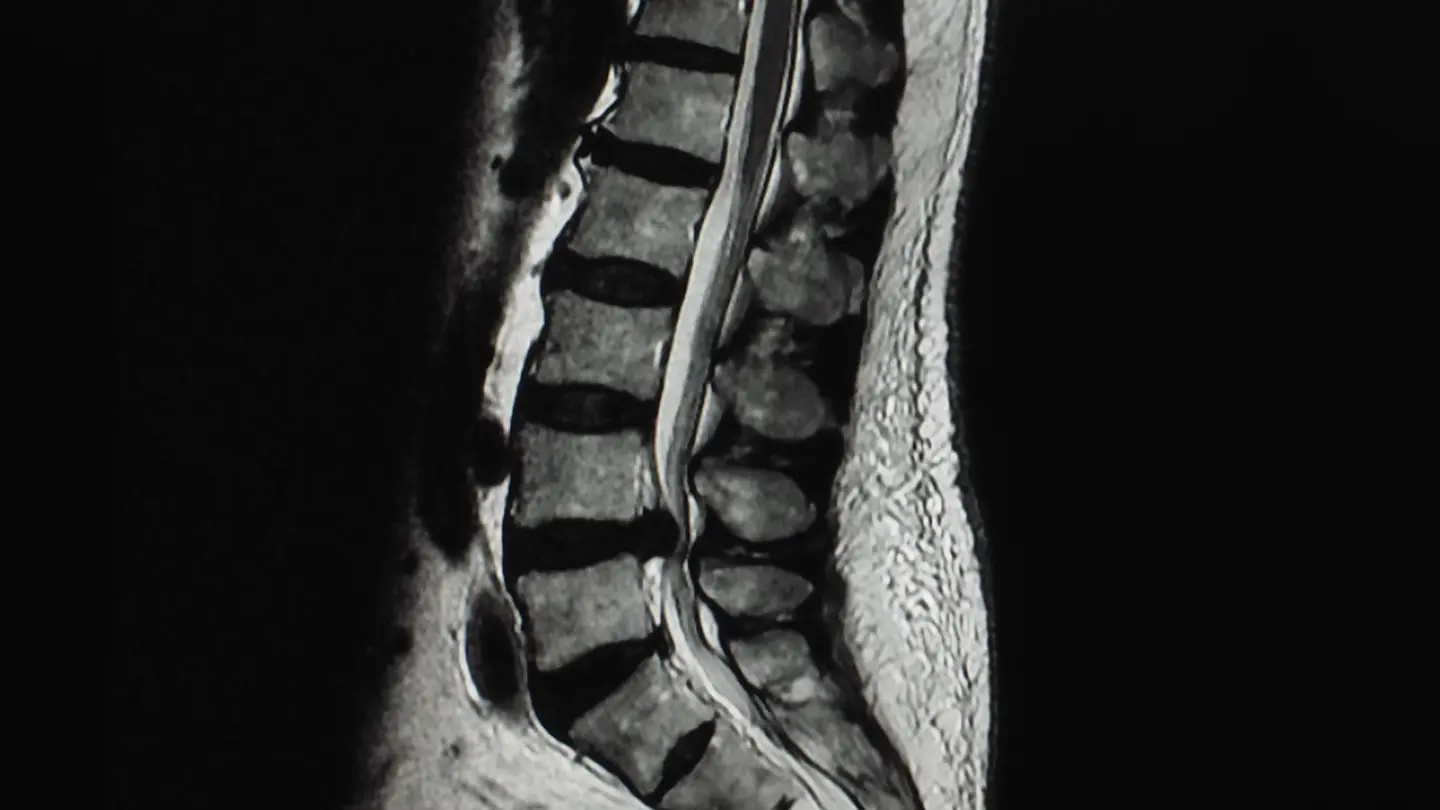

Diagnostic spine MRI scan

A spinal MRI scan can comprehensively assess the spine, including the lumbar, thoracic, and cervical regions, to identify any abnormalities or conditions affecting these areas.

A spine MRI scan can focus on one of three defined areas of the spine, depending on your symptoms and where you’re experiencing pain.

What can a spine MRI scan detect?

The results of your private MRI spine scan could help diagnose a range of injuries or conditions, including:

• Spinal fracture

• Improper spine curvature

• Inflammation

• Spinal cord damage

• Pinched nerves

• Spinal congenital defects

• Herniated discs

• Cervical stenosis

• Infections

• Tumours

A spine MRI scan is a diagnostic tool, so it won’t treat these conditions. However, the results will allow your physician to make informed decisions and recommend appropriate treatment.

MRI Lumbar Spine L5 S1 Level